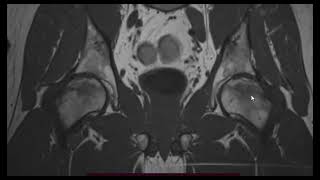

Подтаранный сустав) art. subtalaris